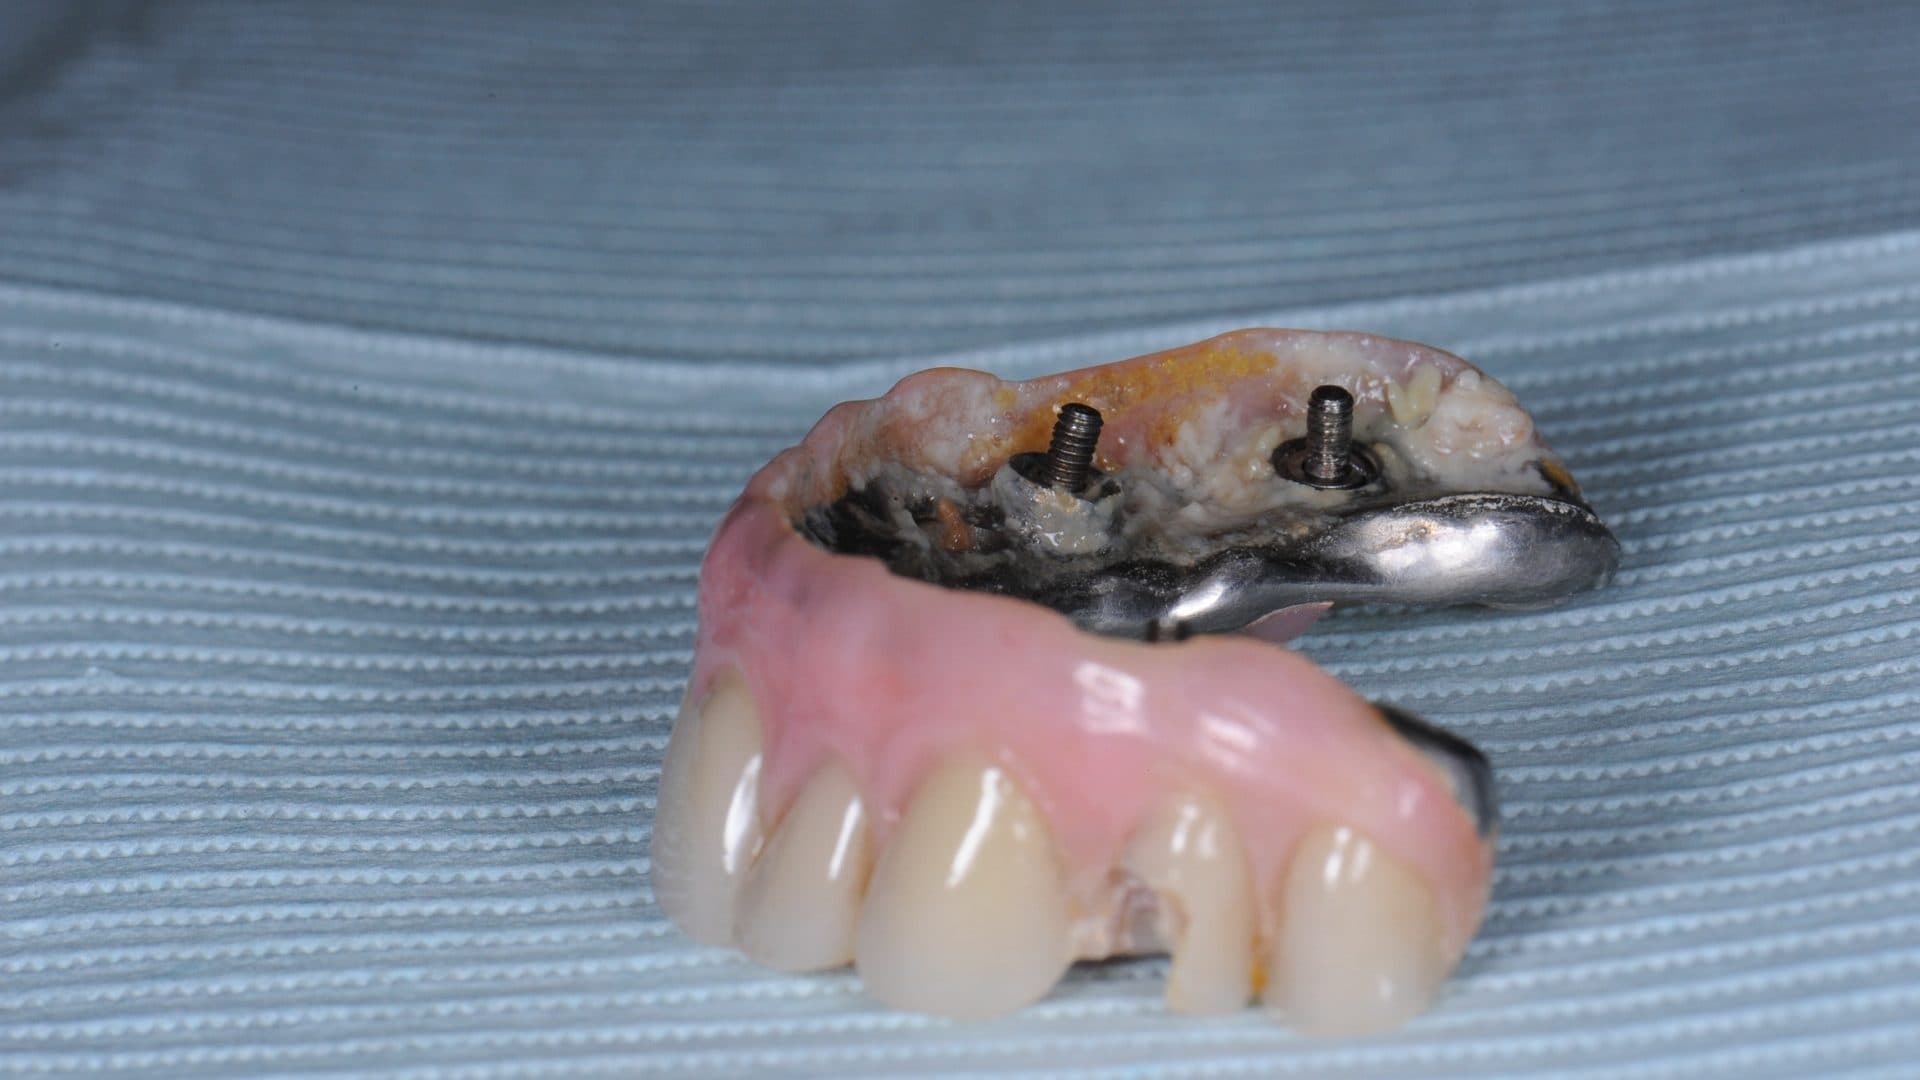

The implants in the picture below were also clean at one time, and probably looked great before the wear and tear, but click through on the picture to see the damage done when implants are placed incorrectly, causing the teeth to be bulky and impossible to clean.

i. Even spread of the implants and flat and uniform under-surface/interface between the prosthesis and the natural gums. A deviation from this will affect the cleanability of the prosthesis, food entrapment and smell (See pictures);